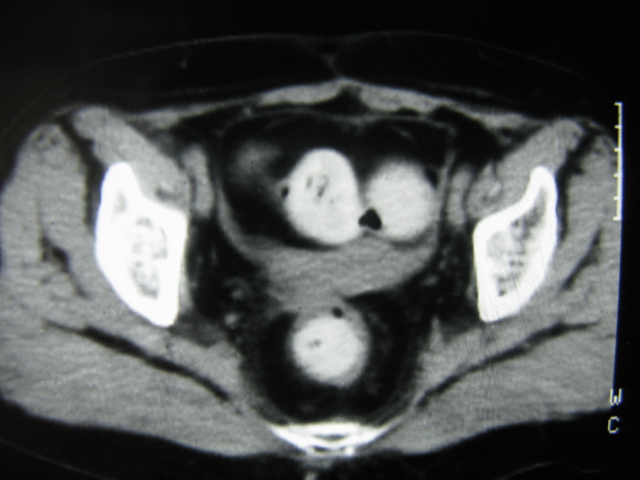

患者,女,64岁,2002年诊断为宫颈癌,当时只做过放,化疗。现在诊断:(1)宫颈癌。(2)直肠癌。请同道们讨论,探讨。另外肠壁为啥密度这么高,ct值约112hu。患者没有做过增强和造影。

高密度的不是肠管影,是肠管内的粪便影

患者直肠病变,排便不畅,粪便硬结造成,更高密度如钡灌肠者都可出现

硬结粪便能有如此高密度影?

我也碰到过几例,最离奇的一例是全结肠呈造影样高密度,患者直肠癌(首次发现),以往没有吃药,只有约半年时间长的胃纳差,排便不畅(据患者说每次大便只能拉出少许黄水)

不一定有意义,可清洁灌肠后复查